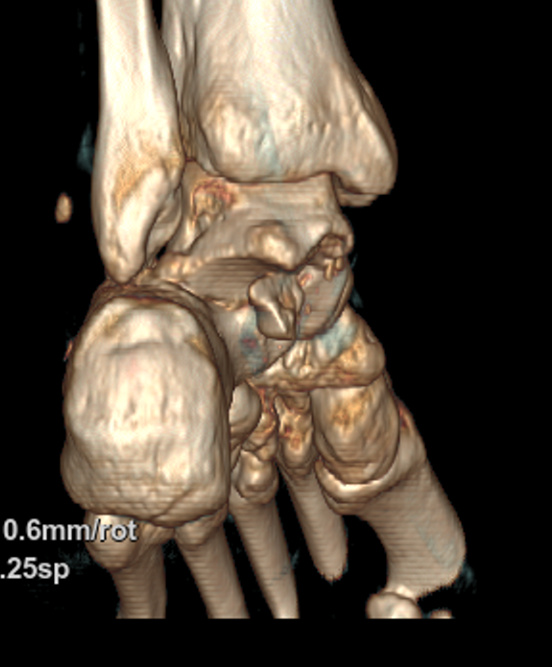

2025年国庆中秋双节期间,58岁的患者赵大哥(化名)紧急被送往北大人民青岛医院成人急诊科。约2小时前,他不慎被重物砸伤左足踝部,当即出现剧烈肿痛。经CT检查,赵大哥左侧距下关节脱位,同时伴有左距骨、腓骨、跟骨多处骨折,以及距腓前韧带断裂、距骨软骨损伤。

△左上、左下、右侧图片分别为术前三维侧面、后面、前面